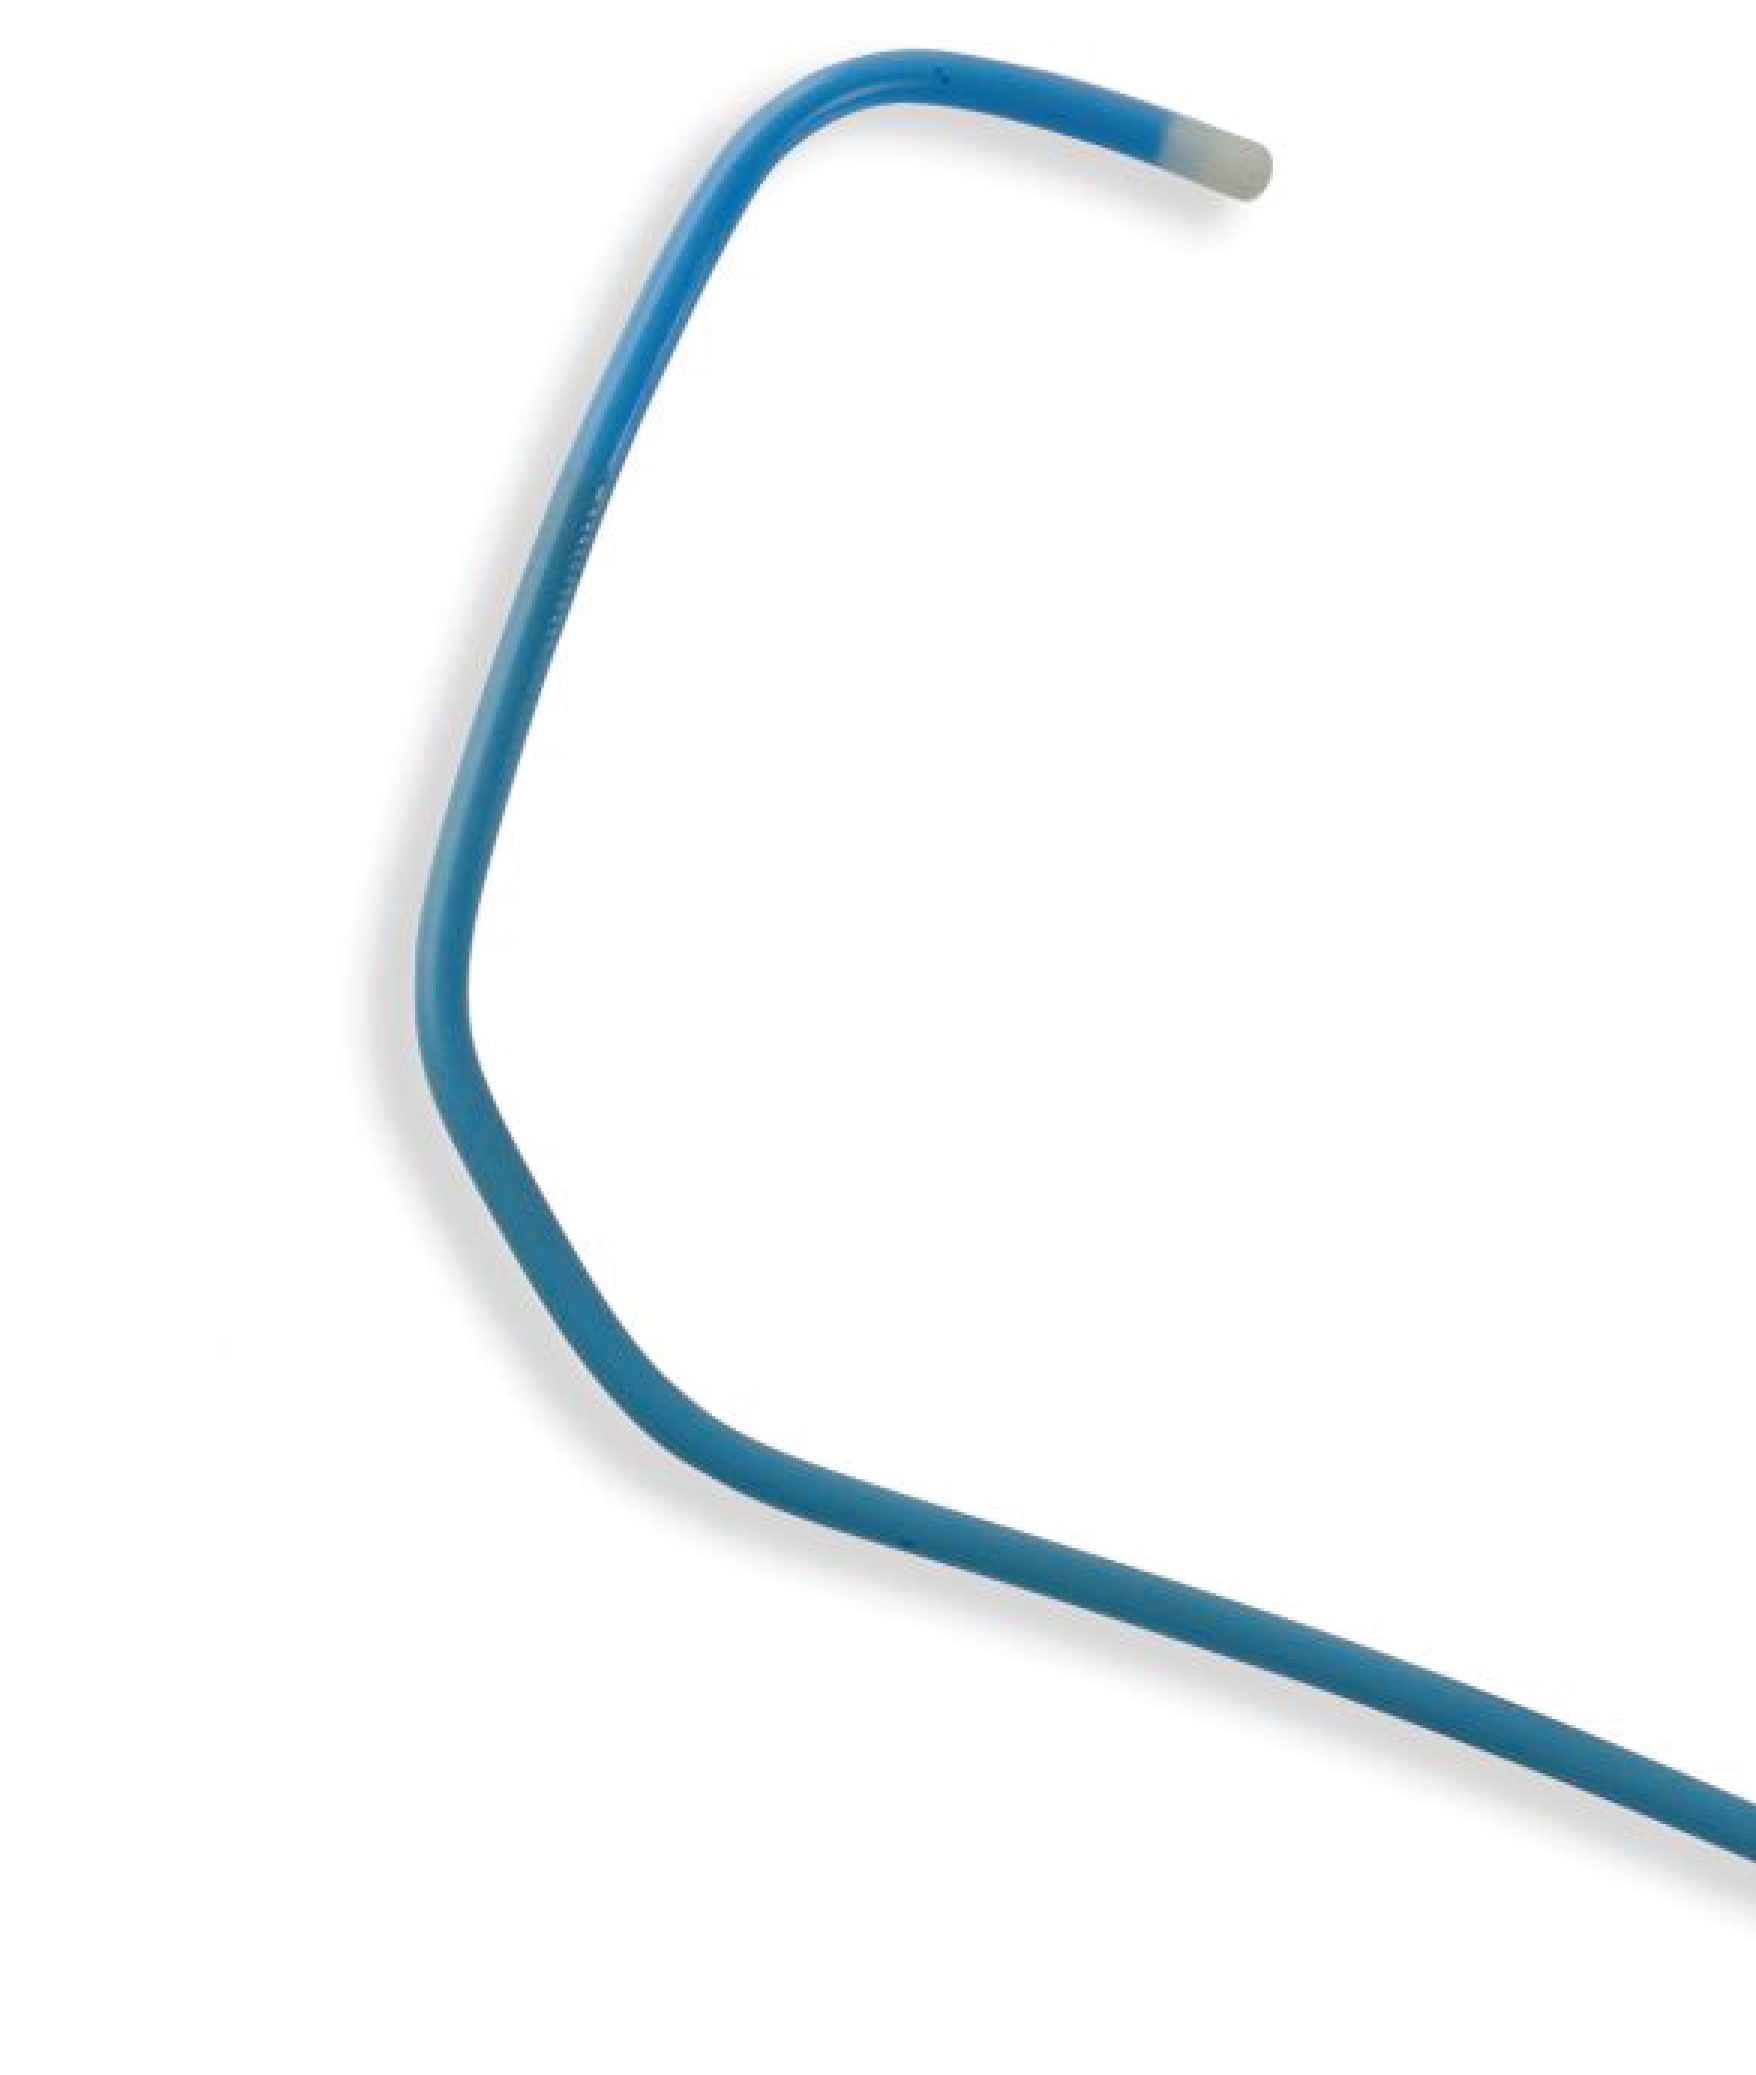

Radial Diagnostic Catheter

• Lower cost per procedure - Engages with simple clockwise & counter clockwise rotation

- Soft tip reduces potential for vessel trauma

- High Flexibility

- Superior Surface Smoothness

- Atraumatic soft tip